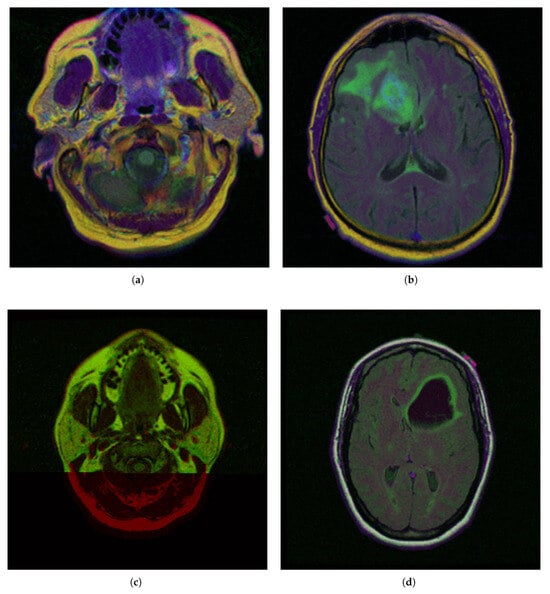

To demonstrate the iMIA application’s work with fuzzy approaches, the MRI images TCGA_CS_4941_19960909_3, TCGA_CS_4941_19960909_14 and two images, segmentation masks for FLAIR abnormality based on TCIA [62] and approved by a certified radiologist at Duke University [63], TCGA_DU_5872_19950223_1 and TCGA_DU_5872_19950223_35 (see Figure 2), were chosen The MRI images are further referenced using the abbreviations: CS1, CS2 and DU1, DU2, respectively.

Figure 2. Selected medical MRI dataset from The Cancer Imaging Archive (TCIA) [62] and certified by Duke University experts [63]: (a) TCGA_CS_4941_19960909_3 (CS1), (b) TCGA_CS_4941_19960909_14 (CS2), (c) TCGA_DU_5872_19950223_1 (DU1), (d) TCGA_DU_5872_19950223_35 (DU2).

In the segmentation masks (e.g., CGA_CS_4941_19960909_3_mask.tif), different colors represent distinct anatomical or pathological regions:

• Red (255, 0, 0)—Tumor core (non-enhancing tumor + necrotic core)

• Green (0, 255, 0)—Edema (swelling around the tumor)

• Blue (0, 0, 255)—Enhancing tumor (region showing contrast enhancement)